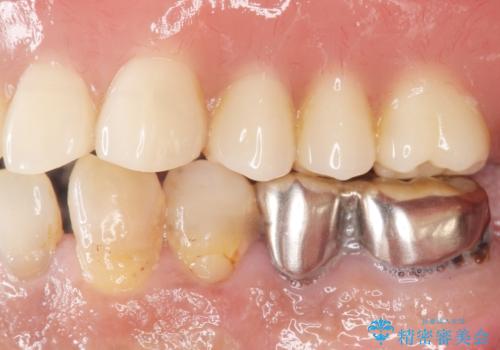

予算を抑えて審美的に咬合を回復することができ、ご満足頂けました。

マグネット(磁石)により入れ歯がはずれにくく動揺しにくいため、入れ歯安定剤などを使うことなく食事やお話も問題なくできると喜んで下さいました。

入れ歯の種類:金属床義歯 マグネットデンチャー

- ¥780,000 (根管治療×2本、土台×2本、磁性アタッチメント×2、金属床義歯)費用は治療当時の料金となります